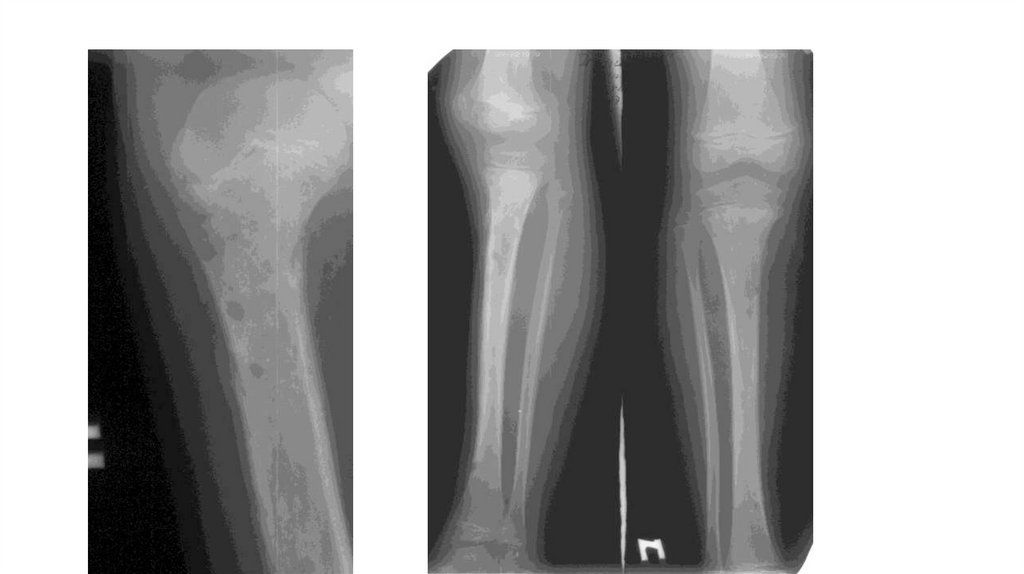

Воспалительные заболевания опорнодвигательного аппарата

«Воспалительные

заболевания опорнодвигательного аппарата»